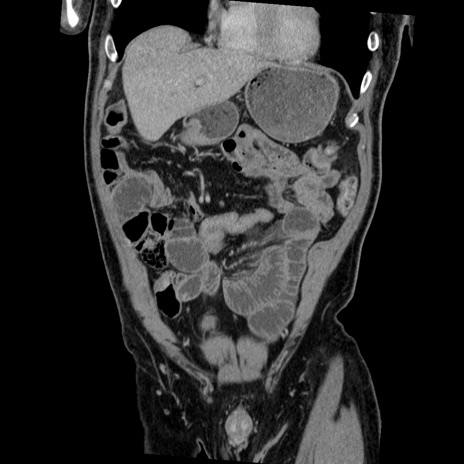

症例22(冠状断像)

【症例】50歳代男性

【主訴】腹痛

【現病歴】AVMからの被殻出血のため回復期リハ病棟入院中。 本日午後3時頃急に下腹部痛が出現した。

【既往歴】AVM、被殻出血、虫垂炎、高血圧

【身体所見】意識晴明、左半身不全麻痺、会話の理解は良好、36.5°C、腹部:膨隆、全体に板状硬、下腹部正中に圧痛点あり、反跳痛-、筋性防御不明、右下腹部にope scar

【データ】WBC 9400、CRP 0.06

横断像